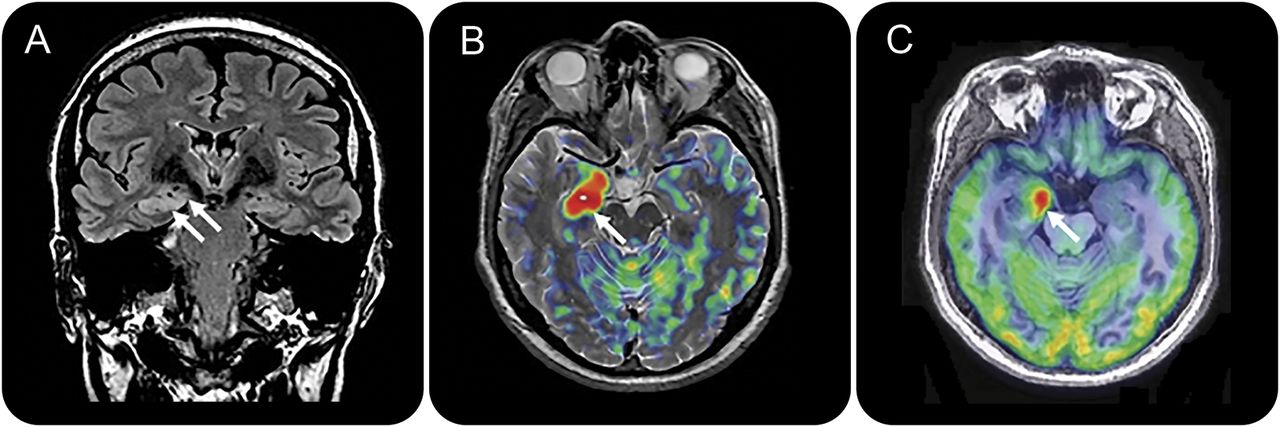

图2

神经影像学自主癫痫持续状态的治疗后由于anti-LGI1脑炎

癫痫在inmunomodulatory治疗控制。治疗一年后,后续日冕fluid-attenuated反转恢复序列(一个)显示完整解决炎症涉及颞中部地区(箭头),而美国手语(B)和18F-FDG-PET (C)显示略有减少血液灌注和新陈代谢的海马和杏仁核(箭头)。